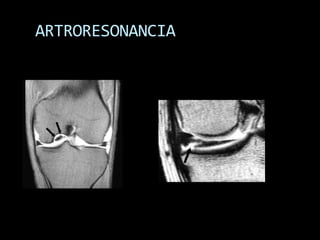

ARTRORESONANCIA

RM: APLICACIONES  Enel campo de la ortopedia: trauma, infecciones y tumores  TRAUMATISMOS ÓSEOS, CARTÍLAGO Y PARTES BLANDAS  Edema óseo, microfracturas trabeculares, fracturas ocultas.  Lesiones ligamentarias-meniscales rodilla  Hombro: impingement, labrum, manguito, inestabilidad (ARTRO-RM)  Osteonecrosis en fase inicial (p.e.j.escafoides, astrágalo)  Columna: lesiones traumáticas, lesiones del disco,…